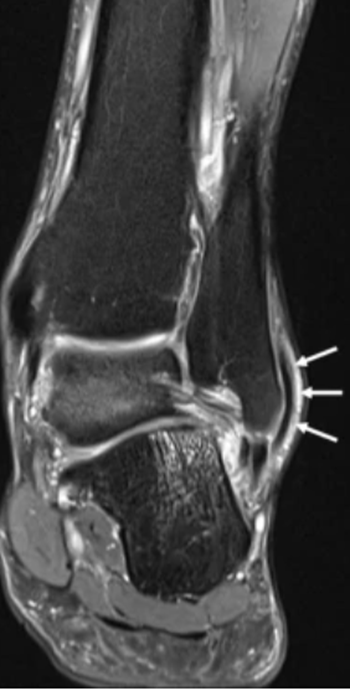

平片和 CT 可能发现腓骨骨片撕脱(斑点征)。MRI 还可用于评估腓骨肌沟的形态及肌腱损伤。

外踝远端斑点征,与腓骨支持带撕脱有关。图源:DOI:10.1302/2058-5241.2.160047。

需要注意的是,平片、CT 和 MRI 是静态影像,无法发现偶发性脱位。